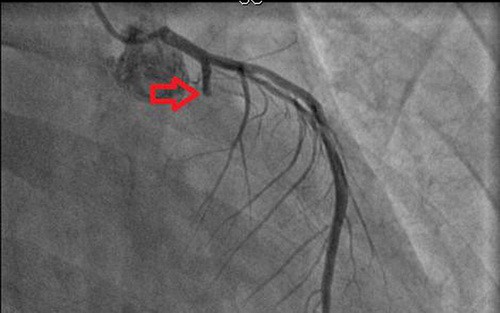

Tại phòng thông tim can thiệp, bệnh nhân được chụp mạch vành bằng máy DSA - máy chụp mạch máu kỹ thuật số xóa nền và xác định chính xác vị trí mạch vành bị tắc hẹp do mảng xơ vữa hoặc huyết khối.

Kết quả chụp cho thấy: Hệ thống mạch máu tim của bệnh nhân hẹp ở rất nhiều vị trí và hẹp rất nặng, nhất là mạch máu tim bên phải. Điều này gây ngạc nhiên cho các bác sĩ vì bệnh nhân tuổi đời còn rất trẻ.

Cảnh giác với nhồi máu cơ tim ở người trẻ - Ảnh 1.

Hình ảnh chụp mạch vành sau khi bệnh nhân 25 tuổi được đặt 1 stent.